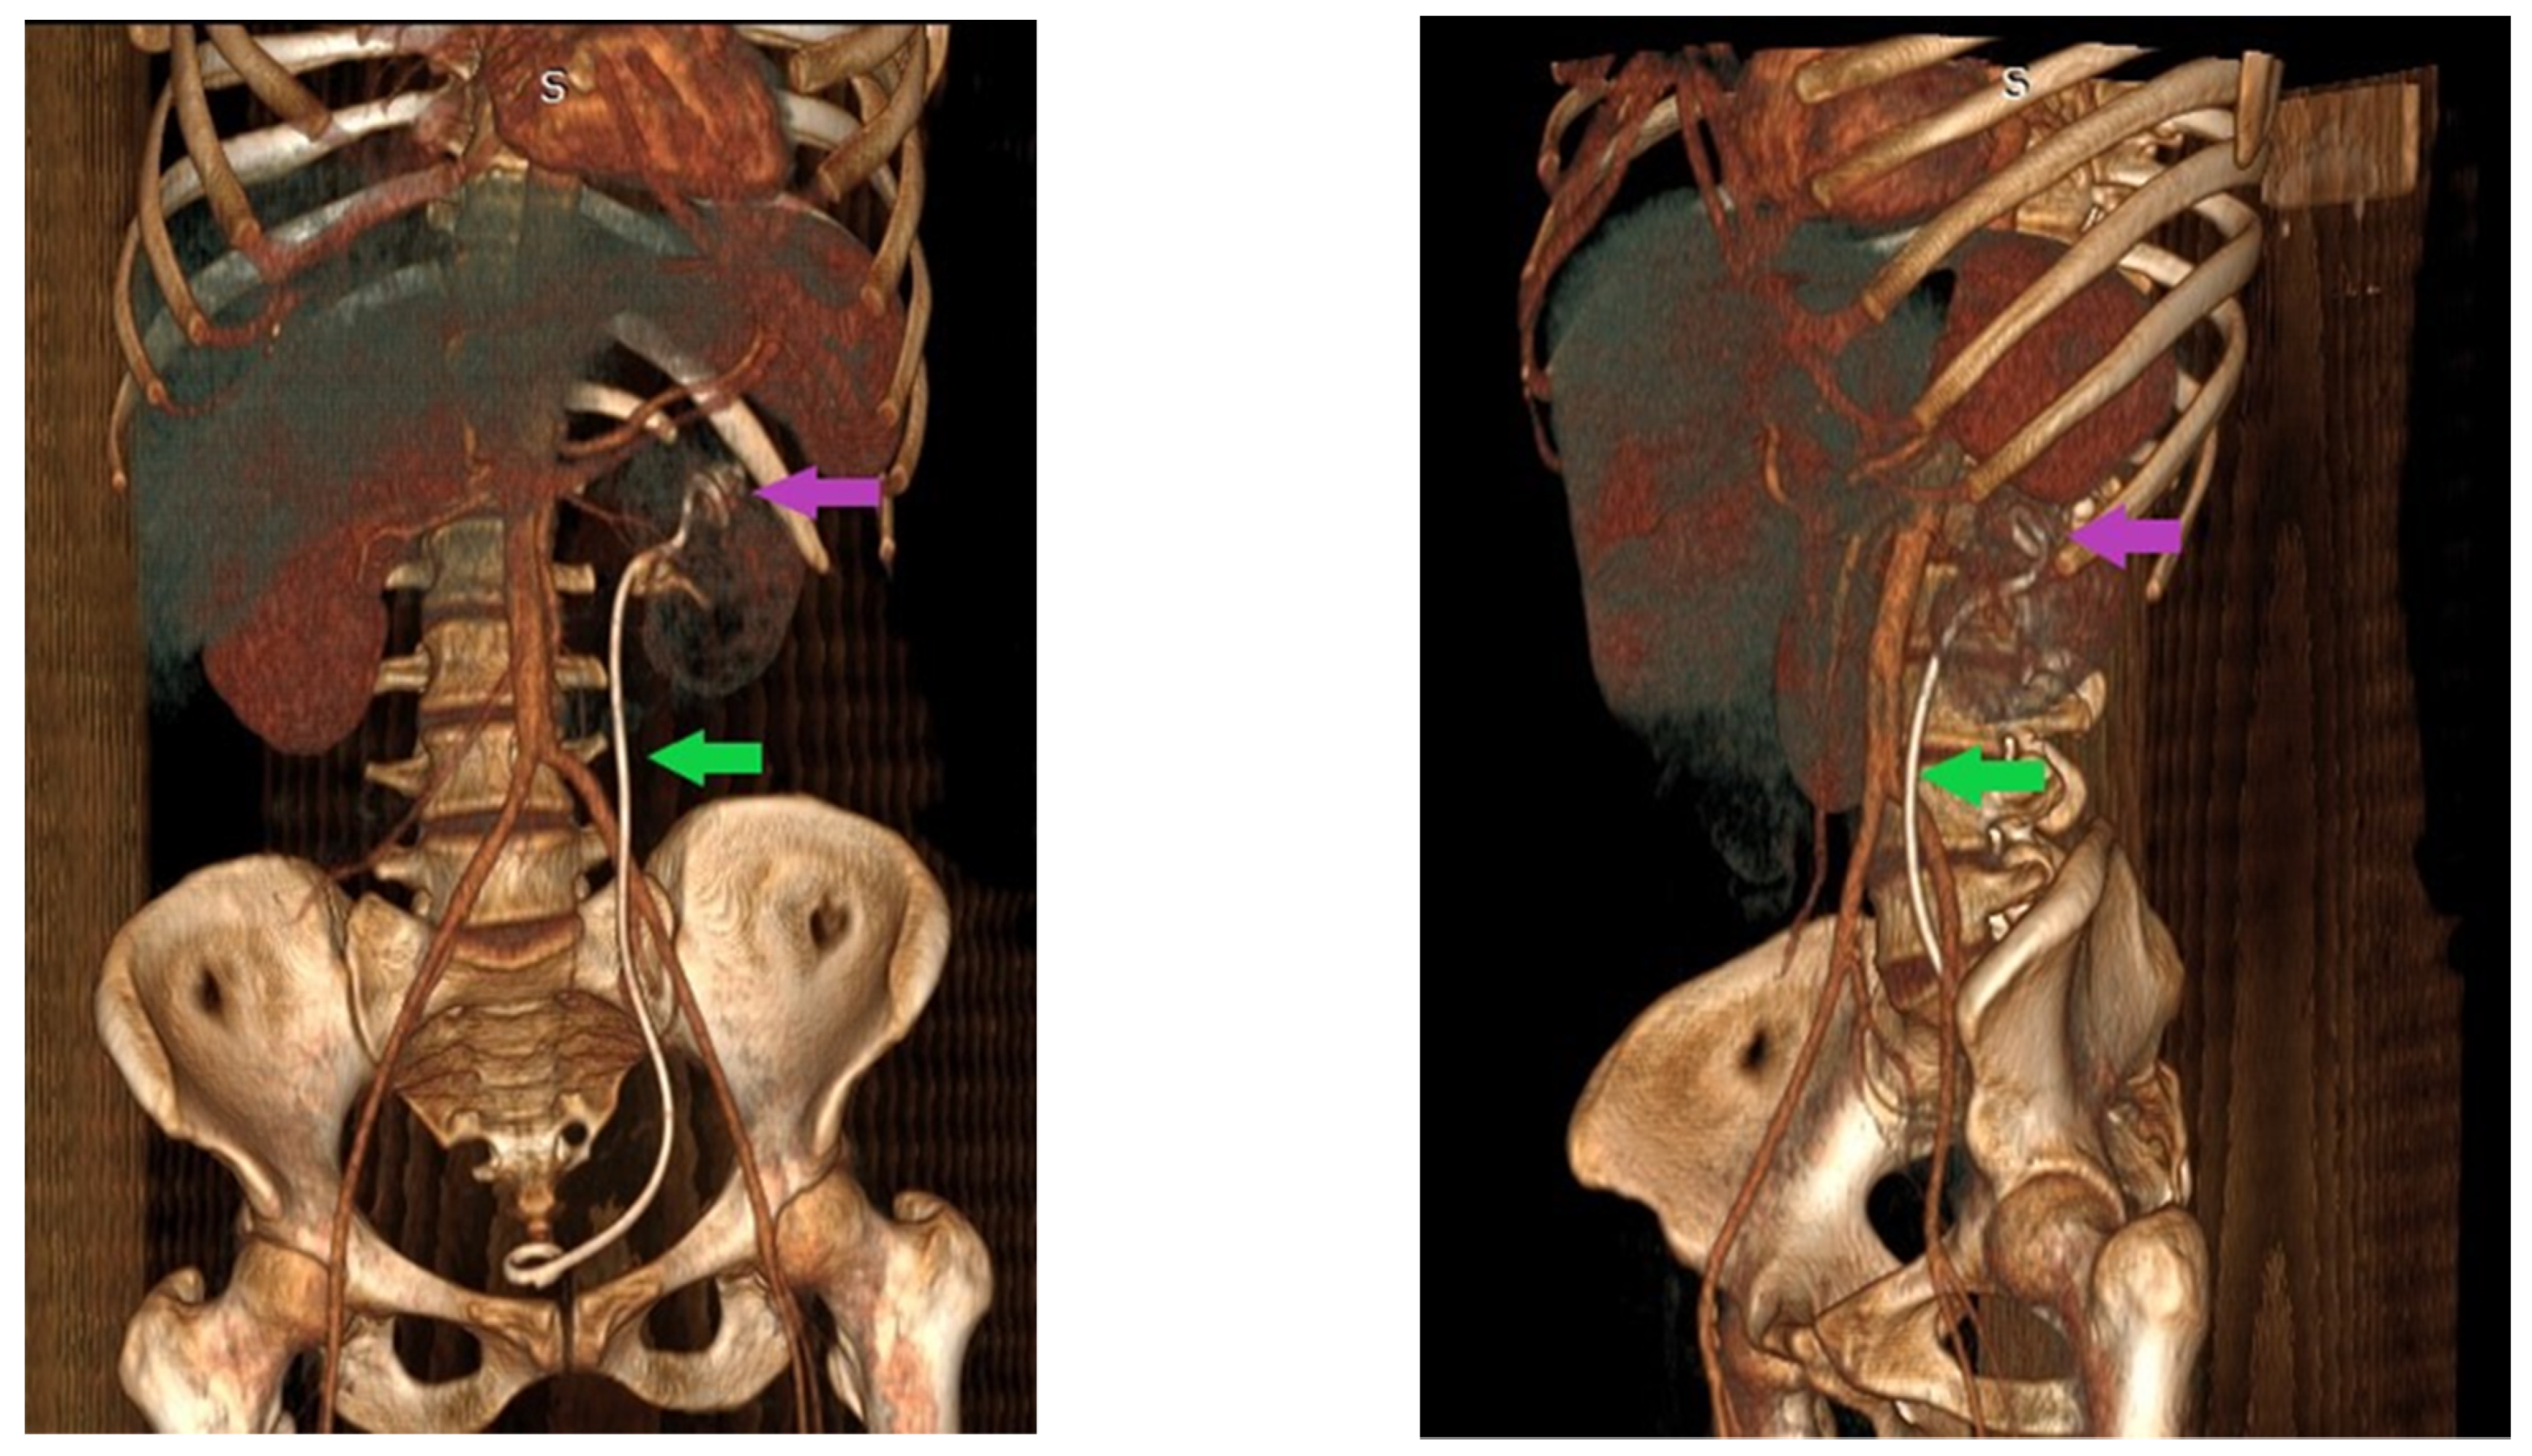

2. Case Report